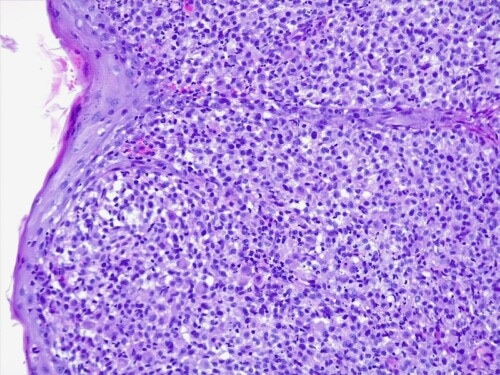

Le derme est envahi par une plage cellulaire dense diffus, peuplé majoritairement de cellules rondes indépendantes présentant une allure histiocytaire, des granulocytes neutrophiles et quelques cellules lymphoplasmocytaires.. Elles sont dotées d’un noyau discrètement plicaturé à chromatine à tendance hyperchromatique finement mottée autour de plusieurs nucléoles. Le cytoplasme est abondant acidophile et présente des limites imprécises. On observe également une anisocaryose, et parfois des cellules plurinucléées, et une forte activité mitotique. Les annexes cutanées sont atrophiées et emprisonnées au sein de cet infiltrat. Aucun élément figuré pathogène parasitaires ou fongiques n’est visible sur la réaction au PAS ni sur les différents de section effectués. L’épiderme est ulcéré et hyperplasique.

L’histopathologie se caractérise par un infiltrat dermique et sous-cutané histiocytaire mal délimité, non-encapsulé. Cet infiltrat se compose de cellules rondes à polygonales à rapport nucléo-cytoplasmique bas, et cytoplasme éosinophilique ou finement granuleux, un noyau ovale ou indenté et chromatine mottée. Un épithéliotropisme – agrégats intra-épidermiques de cellules tumorales – est présent dans une proportion non négligeable , 42% selon la même étude.

Des cellules plurinucléées sont parfois notées, associées à un nombre de mitoses variable. La présence d’atypies cellulaires (pléomorphisme, anisocytose et anisocaryose), d’un index mitotique élevé et de la présence d’emboles intra-lymphatiques ou intravasculaires sont associées à des formes disséminées.